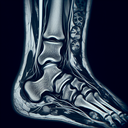

МРТ гомілково-ступневогу суглобу

МРТ гомілково-ступневого суглобу (магнітно-резонансна томографія) – це неінвазивний метод дослідження, який використовує магнітне поле та радіохвилі для отримання детальних зображень м’яких тканин, кісток та суглобів. **Переваги МРТ:** - Висока точність у виявленні пошкоджень зв’язок, сухожиль, м’язів та хрящів. - Відсутність опромінення, що робить процедуру безпечною...